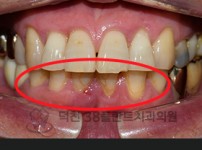

치료전후